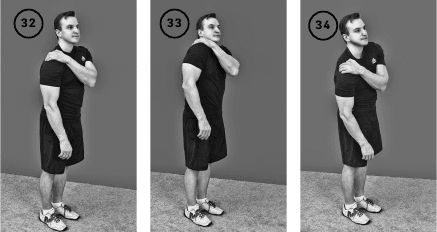

Упражнение «Пожимаем плечом»

Исходное положение – стоя или сидя. Кисть левой руки помещается на надплечье правого плеча, 2-4-й пальцы на лопатке.

Фаза изометрического напряжения: поднимаете правое плечо и надплечье вверх, как бы пожимаете плечом, а левой рукой сопротивляетесь этому движению. Удерживаете позицию изометрического напряжения в течение 20–30 секунд.

Фаза растяжения: теперь расслабьте правую руку, а левой кистью давите на плечо вниз в течение 10–20 секунд, растягивая мышцы, которые перед этим напрягались. Повторить 1–3 раза. Выполнить упражнение для другого плеча (ил. 32–34).